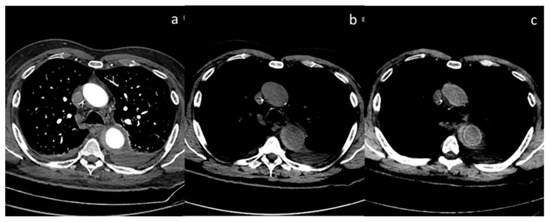

| Volterrani et al. [57] Retrospective study | Italy | To demonstrate the feasibility of DECT for locoregional staging of breast cancer and differentiation of tumor histotypes | 31 | Discovery CT 750 HD, GE Healthcare No C.I. | DECT is feasible and seems to be a reliable tool for locoregional staging of breast cancer. |